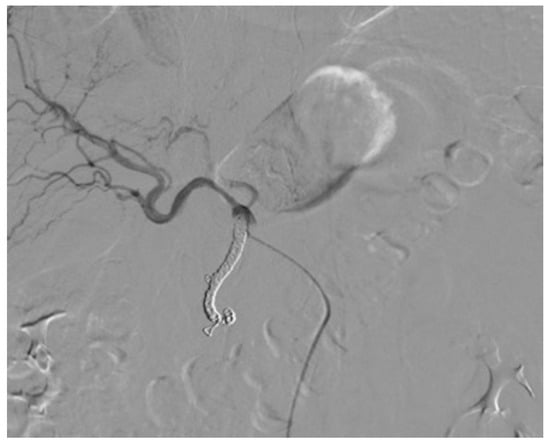

Percutaneous Implantation of a Microcatheter-Port System for Hepatic Arterial Infusion Chemotherapy of Unresectable Liver Tumors: Technical Feasibility, Functionality, and Complications

2.2. Percutaneous Microcatheter-Port System Implantation